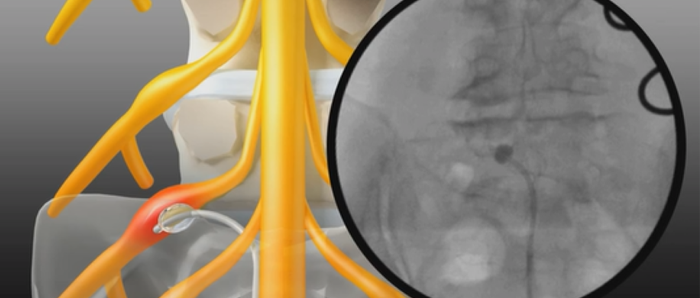

요통, 경추통, 방사통, 척추 골절, 척추 디스크, 척추관협착증, 척추전방전위증,신경차단술, 척추신경성형술, 내시경하 수핵제거술, 척추고정유합술 등

요통, 경추통, 방사통, 척추 골절, 척추 디스크, 척추관협착증, 척추전방전위증, 신경차단술, 척추신경성형술, 디스크고주파 감압술, 양방향 / 단일공 내시경하 수핵제거술, 척추 풍선복원술, 경추/요추 퇴행성질환 교정술 등